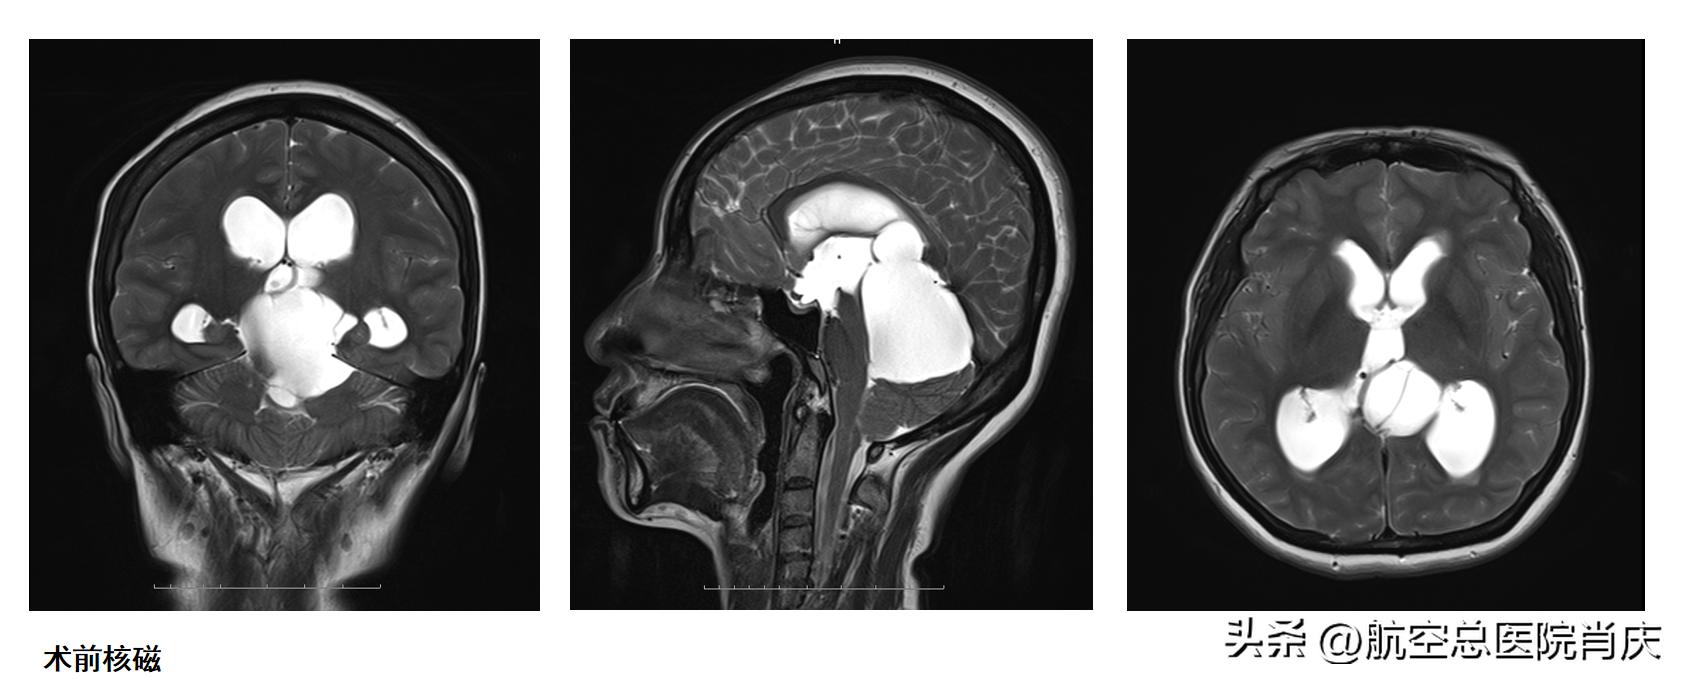

郝女士入院后,积极完善各项术前检查,头颅MRI提示四叠体池囊性病变,脑干、小脑半球及第四脑室受压改变,伴幕上脑室系统扩张。肖庆主任和团队对患者病情进行详细的诊断评估,进行会诊讨论,制定了科学周密的手术方案。

入院五天后,肖庆主任团队为郝女士在全麻下行神经内镜检查术,术中探查第三脑室后部,明确四叠体池蛛网膜囊肿,行蛛网膜囊肿造瘘术,留置脑室外引流管路并连接抗返流引流装置;行第三脑室底造瘘后见基底动脉搏动可,并松解基底池内粘连。术后保持引流通畅并抗炎治疗后,郝女士症状好转,头也不晕不痛了,视力和走路也都恢复了正常,进行头颅MRI及头颅CT复查示脑室系统无明显扩张,囊肿较前缩小,已经可以出院休养。